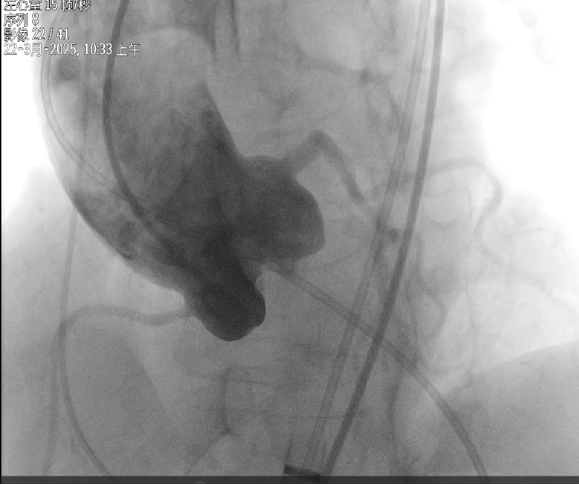

主动脉根部造影